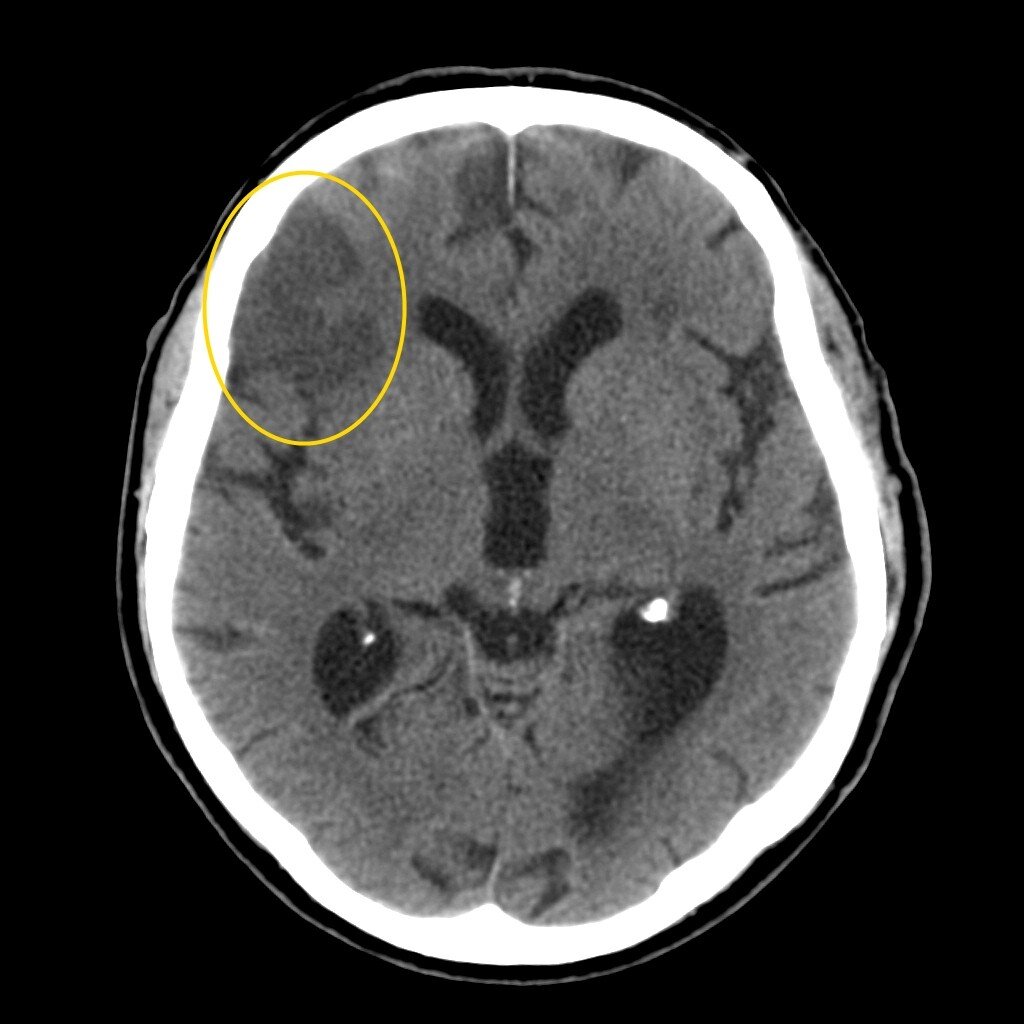

Компьютерная томография показывает участки ишемии головного мозга при инсульте. Ранняя стадия ишемического инсульта визуализируется на КТ только через 4-5 часов в виде сдавливания корковых борозд, а именно набухания (не от слова "бухать"😁) извилин коры головного мозга. По плотности белого и серого вещества (один белый другой серый - два веселых... вещества...😂😂😂) и плотности тканей головного мозга устанавливается вид инсульта и стадия развития.

При второй стадии увеличивается отек мозга, наблюдается гибель вещества мозга, выглядит как затемнение на снимке. На снимке КТ визуализируется снижение плотности белого и серого вещества, отмирают элементы нервной ткани, образуются макрофаги - клетки которые переваривают остатки погибших клеток (как то так, точно не скажу😁).

Ниже приведу примеры снимков КТ головного мозга при инсультах.

Ишемический инсульт (фото из открытых источников)